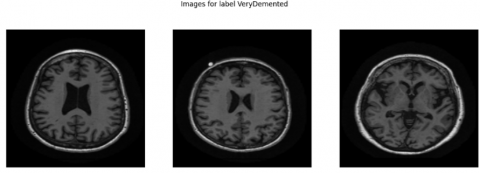

The structural parameters of this dataset show mild bias since it contains 1,216 NonDemented scans while MildDemented scans reach 1,792 images and VeryDemented scans total 706 images. The research data shows good clinical accuracy because healthcare professionals routinely examine more patients with MildDemented conditions. This visual representation in Figure 2 shows MRI cutting planes from each class to represent their structural and intensity differences. The anatomical differences between samples in cognitive processing centers become noticeable in these examples which supports accurate model functioning during training and inference. The varied content of this database enables deep learning models to become effective while they demonstrate multispectral capabilities for AD detection at an early stage.

Figure 2. Sample MRI images from different classes

A proper Exploratory Data Analysis (EDA) was performed in advance to uncover the structural features alongside visual elements and distribution imbalances throughout the dataset. The underlying database consists of 3,714 T1-weighted brain MRI images containing clinical labels of NonDemented, MildDemented and VeryDemented cognitive stage classifications. The three stages of AD organize into separate categories which the labels represent. The main goal of Exploratory Data Analysis included two objectives: first displaying representative images from each class category as shown in Figure 2 and second applying analysis techniques to examine statistical properties which would guide further preprocessing steps and model development.